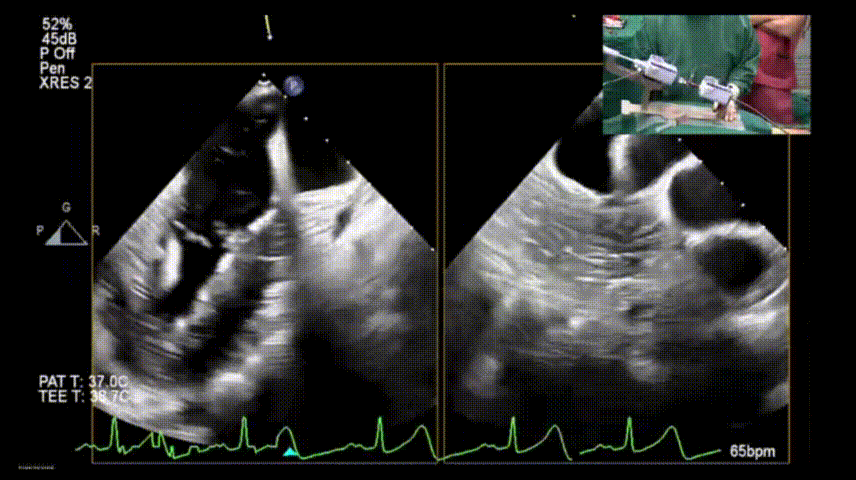

术前食道超声示二尖瓣大量偏心反流

图片

肺静脉血流频谱呈收缩期反向

术前食道超声示二尖瓣大量偏心反流,腱索断裂伴后瓣脱垂